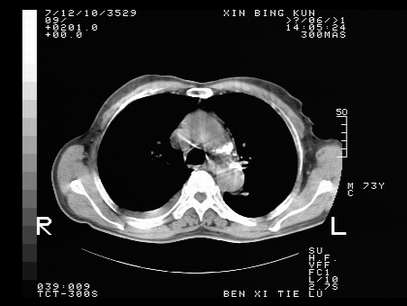

标题: CT10820:男,73岁,病史肺TB,现病史肺炎,直肠CA术后 [打印本页]

标题: CT10820:男,73岁,病史肺TB,现病史肺炎,直肠CA术后

双肺间质改变,依据病史双肺多发结节灶考虑转移,少量胸水.

1.两肺结核.2.两肺多发转移瘤.3右侧少量胸腔积液4.主动脉钙化.

双肺多发结节及条片状致密影,右侧少量胸腔积液。临床:直肠ca术后,肺tb病史。综合考虑:1 双肺转移!2 继发性肺结核合并感染!

此人病史较复杂,原有肺结核,直肠癌术后。肺部病灶形态亦呈多形性。因此,不可仅以一种病来解释肺部的病变。双肺多发的类圆形结节灶,结合病史还是首先考虑转移瘤,而双肺其余病灶还需结合化验室检查,结核或肺部感染在无其它检查资料的情况下不好排除。还是那句话----放射科医生不是开照像馆的,我们也是医生,看片一定要多结合临床及其它检查资料。要当一名合格的放射科医生,并不比当一名临床医生容易,我们可别把自已不当医生看。

两肺多发结节影,并见滋养动脉与其相连,考虑 两肺转移. 右侧胸腔积液考虑胸膜转移.

左肺上叶下叶背段,右肺中下叶见多发斑片状、条索状高密度影,兵变周围小结节影形成“树芽”样改变。 左肺上叶舌段近前胸壁处及右肺中叶内侧段见结节影。右侧胸膜腔内见液体密度区。纵隔内未见明确增大淋巴结。考虑左肺上叶舌段近前胸壁处及右肺中叶转移瘤可能性大。两肺继发型肺结核。右侧胸腔积液。